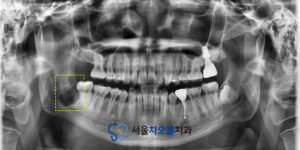

촬영 결과,

오른쪽 아래 사랑니가

정상적으로 맹출하지 못한 채

턱뼈 속에 매복되어 있는 것이

확인되었습니다.

이렇게 매복되어 있는

사랑니 머리 주변으로

낭종이 생겨 있는 것을

확인할 수 있었으며,

이로 인해 주변 조직에 지속적인 자극과

통증이 발생한 것으로 보였습니다.

하지만 매복되어 있는 사랑니와

아래턱 신경관 사이의 거리가 매우 가까워,

발치 시 신경 손상에 대한

위험을 충분히 고려해야 하는

상황이었습니다.

25.12.01 / 25.12.11

치료 전후 사진입니다.